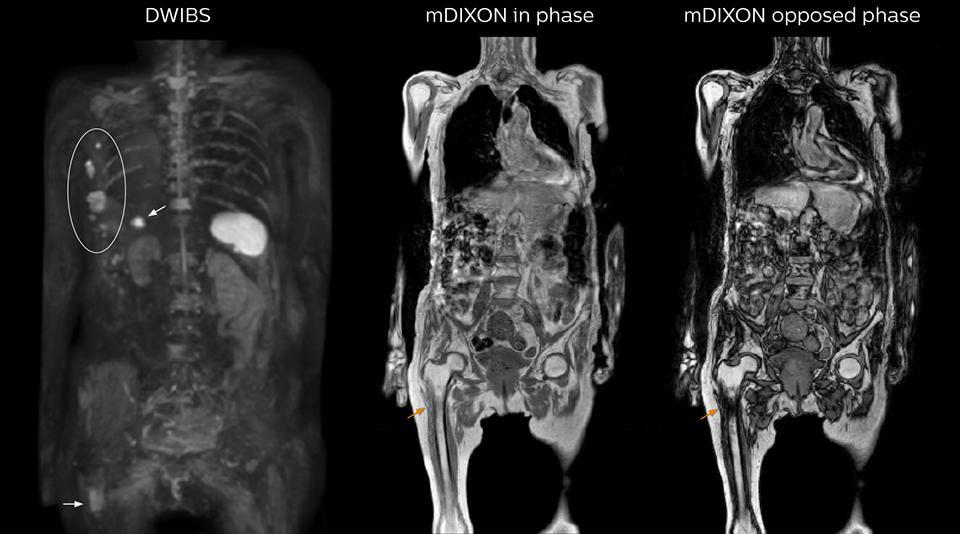

“When we limited the scan coverage to the area from neck to femur, we could fit more clinical information in approximately the same scan time. So, we added coronal mDIXON, sagittal T1-weighted, and sagittal STIR sequences to our examination, instead of performing only axial DWIBS and coronal single-shot TSE scans.” The single shot T2-weighted TSE images are used for morphology and compared to DWIBS images to identify T2 shine-through. Sagittal STIR images are used in patients with inflammation or bone metastasis.

“mDIXON FFE allows us to quickly get information we need to assess the presence of fat. That gives us more information when we need to diagnose bone lesions, and when we are asked to judge fat-containing lesions such as hepatocellular or renal carcinoma,” Dr. Nobusawa says. “The mDIXON fat images can help us to differentiate fatty bone marrow from bone lesions. This is especially useful in elderly people, who tend to have fattier bone marrow. The water images provide a high signal-to-noise ratio in the intestinal canal, which is valuable for visualizing lesions in the colon,” he says.

Kawasaki Sawai Hospital’s whole body protocol also includes an mDIXON FFE sequence. Because mDIXON provides images for four contrast types – water only, fat only, in-phase and out-of-phase – from a single acquisition, it is useful in many ways.

“In-phase and out-phase sagittal T1-weighted FFE images help us to visualize and further characterize bone lesions such as metastasis and bone-marrow hyperplasia that have high signal on DWI. These images are also used throughout radiotherapy, to monitor changes in the fatty bone marrow.”